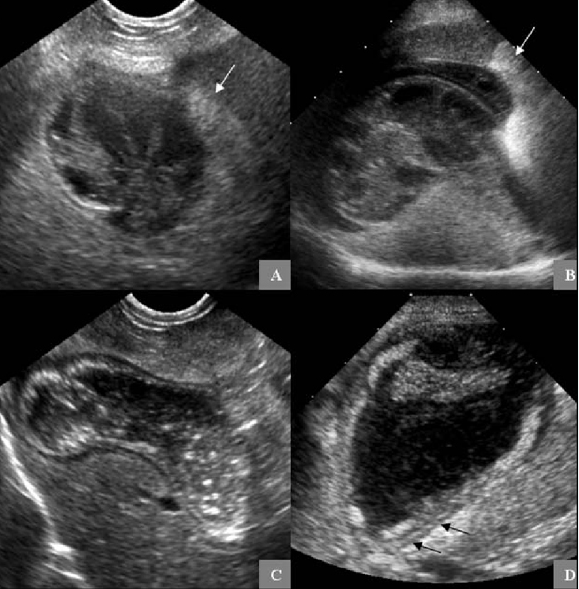

담낭점액종은 담낭벽에 점액이 달라 붙어 있으면서 혈액 순환등에 장애를 주고 염증을 일으키기 쉬워 담도가 막히거나 파열을 일으키는 경우가 종종있다.

하지만 Anicteric gallbladder rupture라는 항목 즉, 무황달성 담낭 파열이 존재하기 때문에 황달이 없다는 이유로 담낭 파열을 배제해서는 안된다.

소량의 복수와 담즙과 관련한 이상이 의심되는 환자가 있다면 무황달성 담낭 파열을 고려해야 하기에 수술적으로 담낭제거를 시행해야 한다는 의미가 되기도 한다.